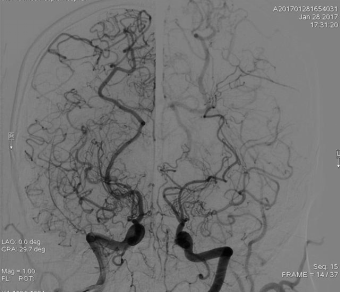

吴红红烟雾病2019.10.18脑血管造影图像